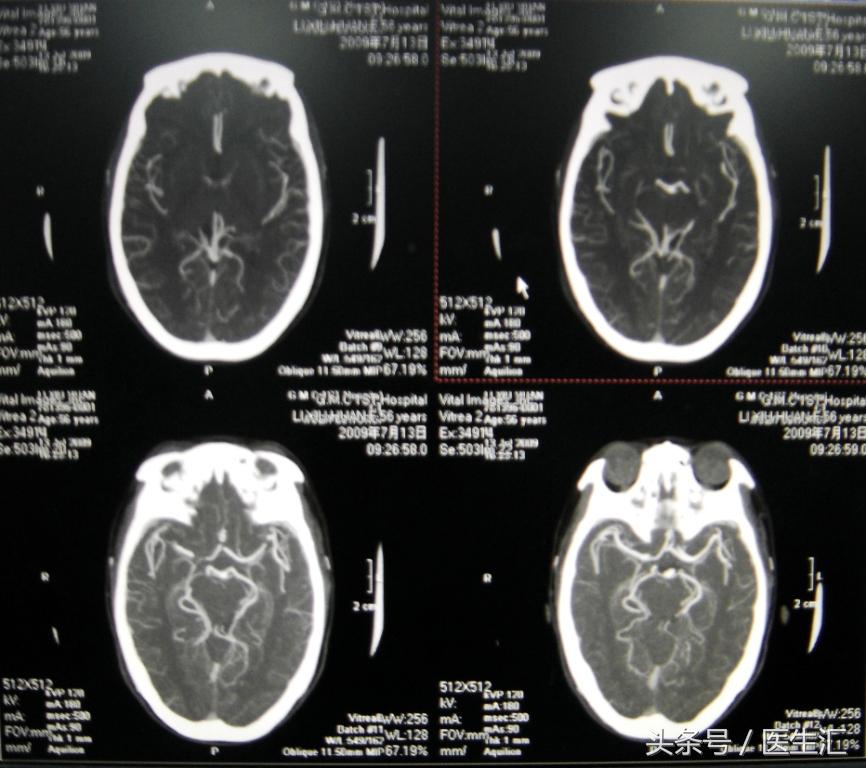

2、头颅MRI、MRA及脑血管三维重建(图12、13、14)